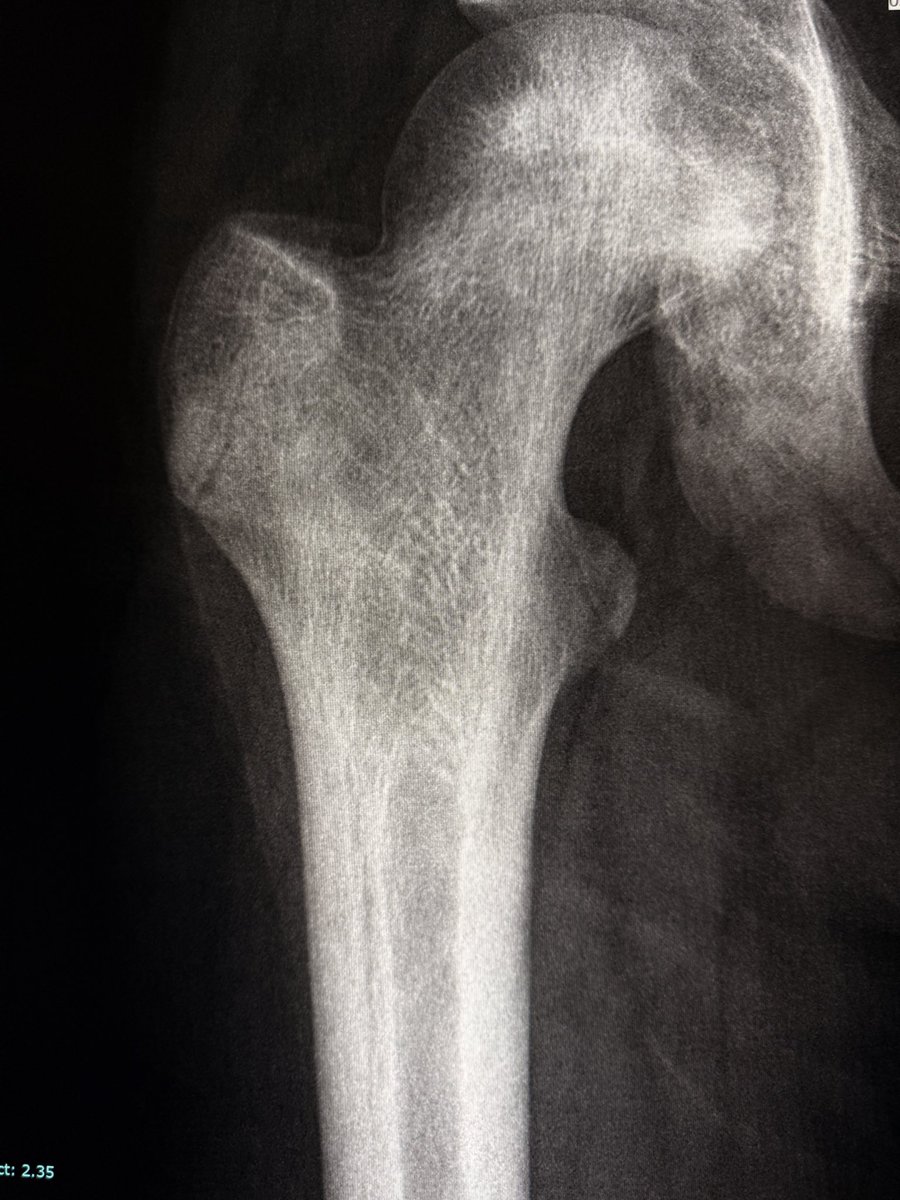

“Bone within bone” appearance of proximal femoral diaphysis in sickle cell disease. This appearance is due to chronic medullary bone infarction with a sclerotic rim (reflecting the new bone formed around old infarctions). The lucent rim between the cortex and the medullary

“Bone within bone” appearance of proximal femoral diaphysis in sickle cell disease.

This appearance is due to chronic medullary bone infarction with a sclerotic rim (reflecting the new bone formed around old infarctions).

The lucent rim between the cortex and the medullary